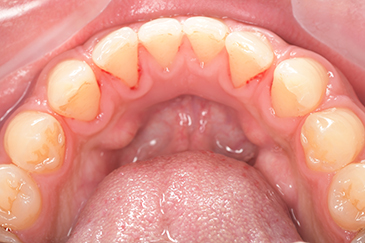

CASE 5

| 年齢・性別 | 19歳・女性 |

|---|---|

| 主訴 | 定期検診 |

| 治療内容 | PMTC |

| 治療期間 | 30分 |

| 治療費 | 5,500円 |

| リスク・副作用 | 知覚過敏 |

| 治療方針 | スケーリングしてから着色を除去しました。着色は一度綺麗に落としても再度付着するため、今後は定期的なクリーニングを行います。 |

| 担当者所見 | 歯ぐきに色素が沈着しているためガムピーリングとホワイトニングを行うことで、より明るく見えるようになります。 |